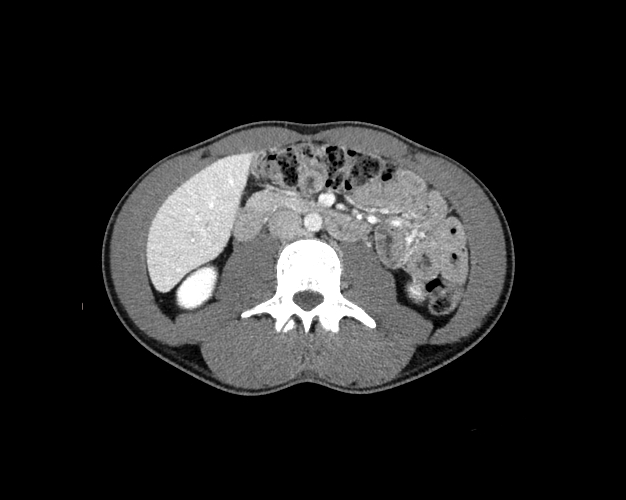

Body

Covers abdominal CT anatomy.